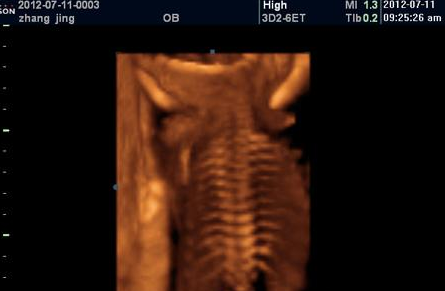

四维彩超:

过去的B超设备只能检查胎儿的生理指标,而四维彩超还能对胎儿的体表进行检查,如唇裂,脊柱裂,大脑、肾、心脏、骨骼发育不良等,以便尽早的进行治疗。生个聪明健康的小宝宝,并且将宝宝的样子和动作制作成照片或DVD,让宝宝拥有最完整的0岁相册,这已经不再是幻想。